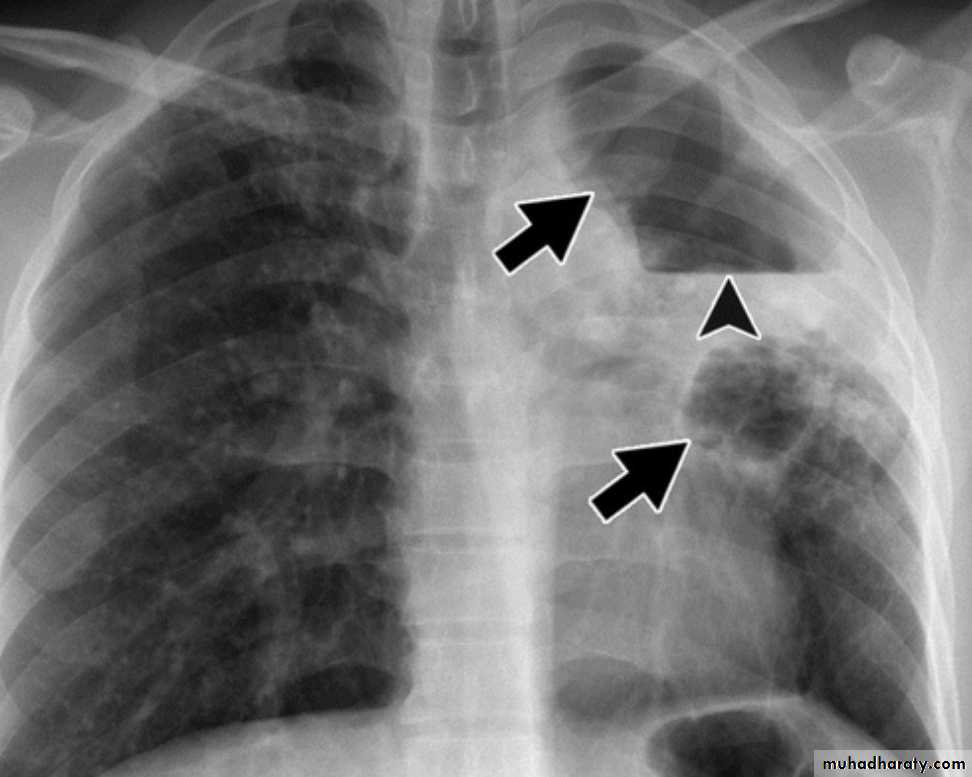

* or enter through the lymphatic channel or blood stream causing Miliary TB. or isolated organ TB.

1- Miliary tuberculosis with multiple tubercles in numerous organs & tissues.2- Isolated metastatic organ lesions e.g., in kidney, bone, vertebra, joint & epididymis.